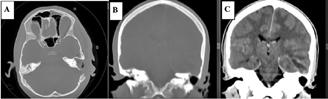

• Studiul opacifierii ramurilor corticale ale arterelor cerebrale medii (M4) drepte și stângi și a venelor cerebrale interne drepte și stângi (Fig.1).

Fig.1 ACTMS cranio-cerebrală, recon MIP în plan axial (a,b) și sagital (c): aspect normal; (a) opacifierea arterelor temporale dreaptă și stângă (săgeţi); (b) opaciferea ramurilor corticale ale arterelor cerebrale medii (M4)-săgeţi albe; opaciferea venelor cerebrale interne dreaptă și stângă (săgeţi negre-b și c).

Semiologie:

▶ Absența opacifierii M4 = 1 punct

▶ Opacifierea M4 = 0 punct

▶ Absența opacifierii venei cerebrale interne = 1 punct

▶ Opacifierea venei cerebrale interne = 0 puncte

• Un scor egal sau mai mare de 3 confirmă stopul circulator intracerebral. In acest caz, concluzia examinării este: „stop circulator intracerebral” care vine în sprijinul diagnosticului clinic de moarte cerebrală sau aspect ACT compatibil cu moartea cerebrală

• În caz contrar, concluzia examinării este „absența opririi circulatiei intracerebrale”, situaţie în care diagnosticul clinic de MC nu este confirmat.